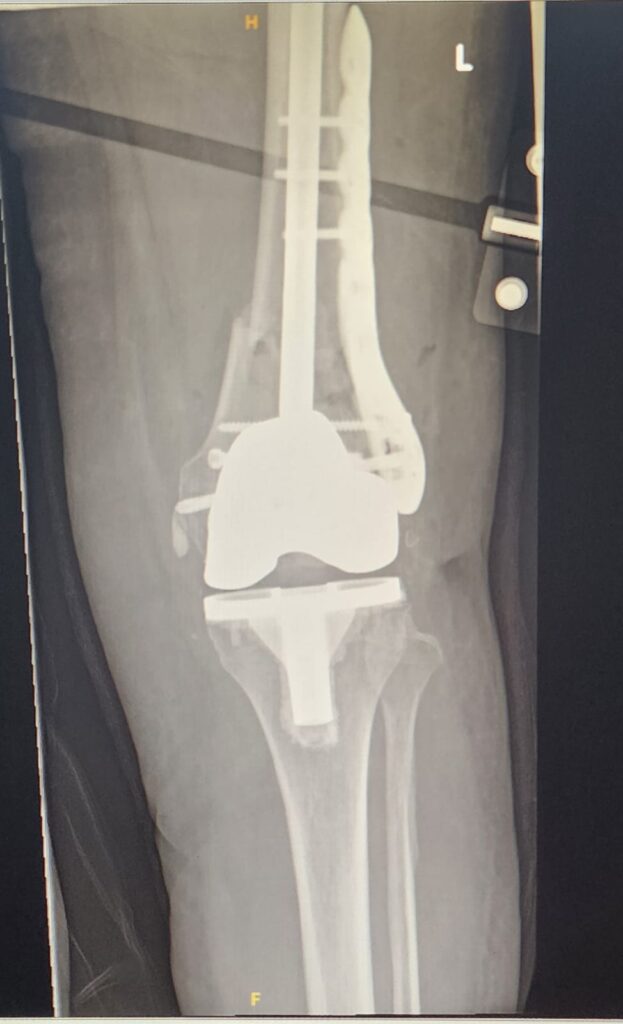

πŸ“Έ Intraoperative / Post-fixation X-rays

(Image 3 & 4) – Postoperative radiographs show the interlinked construct in place, providing optimal alignment and stability.

This technique allows immediate weight-bearing and controlled knee movement in a hinged brace.